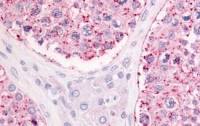

SEPT5 antibody [N3C3] detects SEPT5 protein at cytosol on human breast carcinoma by immunohistochemical analysis.

Sample: Paraffin-embedded human breast carcinoma.

SEPT5 antibody [N3C3] (GTX118561) dilution: 1:200.

Antigen Retrieval: Trilogy™ (EDTA based, pH 8.0) buffer, 15min